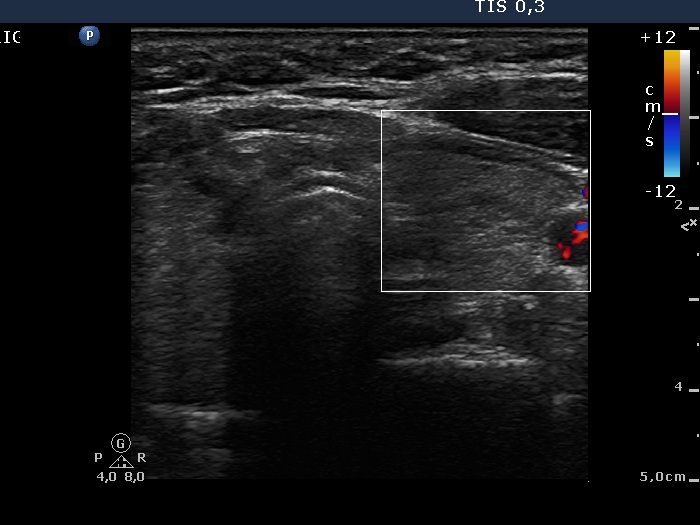

Right lobe, longitudinal scan

Left lobe, horizontal scan. There is a hypoechogenic nodule in the dorsal part of the thyroid.